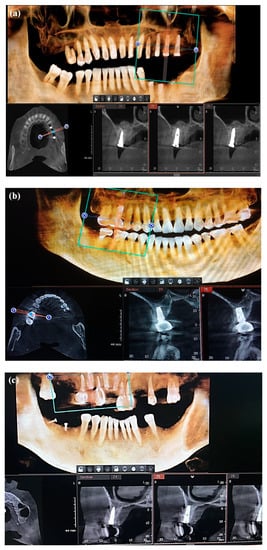

The cone-beam CT images six months follow-up after treatment are presented in Figure 8, which exhibits the presence of ossification in the defect area. Figure 8a shows a cone-beam CT image representing a clinical case six months after bone graft placement in the left maxillary region, while Figure 8b,c represent bone graft placement in the right maxillary region. The presence of bone formation can also be seen in the area around the dental implant apex. Several studies have shown satisfactory results in the sinus lifting treatment accompanied by the placement of bone graft material, and this will affect the survival rate of the dental implant [].

Figure 8.

Cone-beam CT images after six months post-treatment in (a) the left maxillary region, (b) right maxillary molar, and (c) right maxillary premolar.